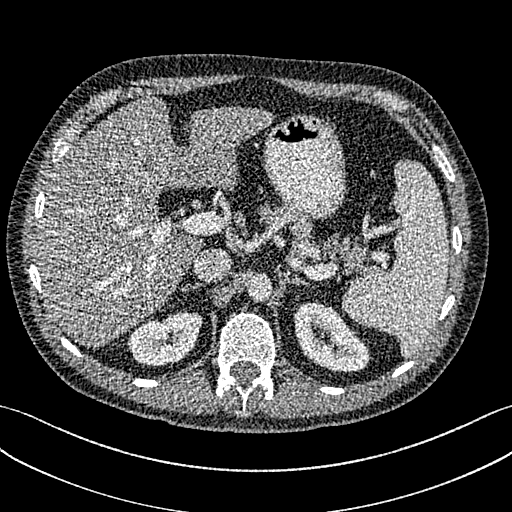

To show the denoising effect of the selected networks, we took two representative slices as shown in Figs. 5 and 7. And Figs. 6 and 8 are the zoomed regions-of-interest (ROIs) marked by the red rectangles in Figs. 5 and 7. All the networks demonstrated certain denoising capabilities. However, CNN-MSE blurred the images and introduced waxy artifacts as expected, which are easily observed in the zoomed ROIs in Figs. 6e and 8e. WGAN-MSE was able to improve the result of CNN-MSE by avoiding over-smooth but minor streak artifacts can still be observed especially compared to CNN-VGG and WGAN-VGG. Meanwhile, using WGAN or GAN alone generated stronger noise (Figs. 6g and 8g) than the other networks enhanced a few white structures in the WGAN/GAN generated images, which are originated from the low dose streak artifact in LDCT images, while on the contrary the CNN-VGG and WGAN-VGG images are visually more similar to the NDCT images. This is because the VGG loss used in CNN-VGG and WGAN-VGG is computed in a feature space that is trained previously on a very large natural image dataset [48]. By using VGG loss, we transferred the knowledge of human perception that is embedded in VGG network to CT image quality evaluation. The performance of using WGAN or GAN alone is not acceptable because it only maps the data distribution from LDCT to NDCT but does not guarantee the image content correspondence. As for the lesion detection in these two slices, all the networks enhance the lesion visibility compared to the original noisy low dose FBP images as noise is reduced by the different approaches.

As for iterative reconstruction technique, the reconstruction results depend greatly on the choices of the regularization parameters. The implemented dictionary learning reconstruction (DictRecon) result gave the most aggressive noise reduction effect compared to the network outputs as a result of strong regularization. However, it over-smoothed some fine structures. For example, in Fig. 8, the vessel pointed by the green arrow was smeared out while it is easily identifiable in NDCT as well as WGAN-VGG images. Yet, as an iterative reconstruction method, DictRecon has its advantage over post-processing method. As pointed by the red arrow in Fig 8, there is a bright spot which can be seen in DictRecon and NDCT images, but is not observable in LDCT and network processed images. Since the WGAN-VGG image is generated from LDCT image, in which this bright spot is not easily observed, it is reasonable that we do not see the bright spot in the images processed by neural networks. In other words, we do not want the network to generate structure that does not exist in the original images. In short, the proposed WGAN-VGG network is a post-processing method and information that is lost during the FBP reconstruction cannot easily be recovered, which is one limitation for all the post-processing methods. On the other hand, as an iterative reconstruction method, DictRecon algorithm generates images from raw data, which has more information than the post-processing methods.

To gain more insight into the output images from different approaches, we inspect the statistical properties by calculating the mean CT numbers (Hounsfield Units) and standard deviations (SDs) of two flat regions in Figs. 5 and 7 (marked by the blue rectangles). In an ideal scenario, a noise reduction algorithm should achieve mean and SD to the gold standard as close as possible. In our experiments, the NDCT FBP images were used as gold standard because they have the best image quality in this dataset. As shown in Table III, Both CNN-MSE and DictRecon produced much smaller SDs compared to NDCT, which indicates they over-smoothed the images and supports our visual observation. On the contrary, WGAN produced the closest SDs yet smaller mean values, which means it can reduce noise to the same level as NDCT but it compromised the information content. On the other hand, the proposed WGAN-VGG has outperformed CNN-VGG, WGAN-MSE and other selected methods in terms of mean CT numbers, SDs, and most importantly visual impression.